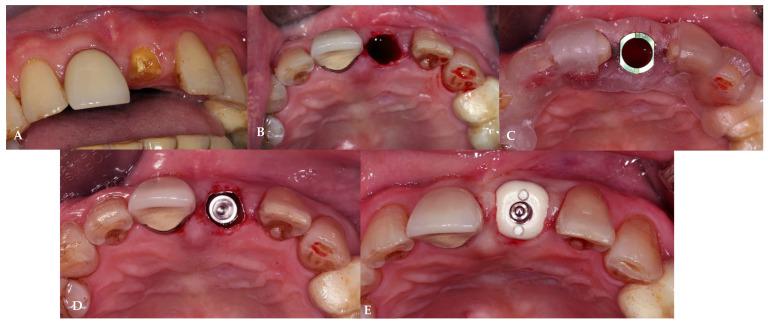

This study aimed to evaluate the effect of customized healing abutments compared to prefabricated healing abutments in immediate implant sites. Twelve patients requiring single immediate implant placement were divided into two groups: a prefabricated group received prefabricated titanium healing abutments, and a customized group received a polyetheretherketone (PEEK) customized healing abutments fabricated based on the individuals' digital impressions. Outcomes, including peri-implant horizontal and vertical soft tissue alteration, bone level change, volume change, pain score, and pink esthetic score (PES) change, were evaluated at the 1-, 4-, and 6-month follow-ups compared to pre-extraction teeth. At the 1- and 4-month follow-ups, the customized group had a significantly lower buccal volume variation (BVv). At the 6-month follow-up, neither group showed any significant difference in the marginal bone change; however, the customized group had a significantly lower PES change and a lower pain score. In the anterior and premolar regions, the customized group showed the preservation of peri-implant buccal horizontal soft tissue and buccal volume, while in the molar regions, the preservation of papilla height and midfacial height was observed. The morphology of the customized healing abutment demonstrated a better trend in preservation of peri-implant soft tissue, esthetic outcomes, and lower patient discomfort in immediate implant sites.

本研究旨在评估在即刻种植位点使用定制愈合基台与预制愈合基台相比的效果。12例需要进行单颗即刻种植的患者被分为两组:预制组接受预制钛愈合基台,定制组接受基于个体数字化印模制作的聚醚醚酮(PEEK)定制愈合基台。与拔牙前的牙齿相比,在1个月、4个月和6个月的随访中评估各项结果,包括种植体周围水平和垂直软组织变化、骨水平变化、体积变化、疼痛评分和粉色美学评分(PES)变化。在1个月和4个月的随访中,定制组的颊侧体积变化(BVv)显著更低。在6个月的随访中,两组在边缘骨变化方面均未显示出任何显著差异;然而,定制组的PES变化显著更低且疼痛评分更低。在前牙区和前磨牙区,定制组显示出种植体周围颊侧水平软组织和颊侧体积得以保留,而在磨牙区,则观察到龈乳头高度和面部中部高度得以保留。定制愈合基台的形态在即刻种植位点的种植体周围软组织保留、美学效果以及降低患者不适感方面呈现出更好的趋势。